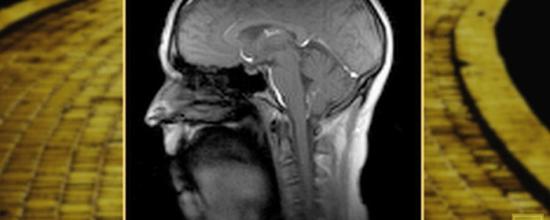

![]() 贝克曼生物医学成像中心的核磁共振仪采集到的人歌唱时的喉部运动图像,采集速度每秒100帧 据国外媒体报道,在唱歌或是说话时,需要人的胸部、颈部、下颚、舌头和嘴唇等处上百种肌肉相互协作才能发出声音。利用新发明的一种超高速核磁共振成像技术,美国贝克曼高等科学技术研究所的研究人员现在能够对这些肌肉的协作进行成像,研究这些协作的进程。 “人能够发出各种声音,能够唱歌,这一点让我感到惊叹”,Aaron Johnson介绍说,他是贝克曼高等科学技术研究所下辖的生物成像科学与技术研究组的成员,语言与听觉科学助理教授,“声音是通过两小片组织震动发出来的。这正是我付出一生对其进行研究的原因:我觉得这太神奇了。” 声音是由位于颈部的喉发出的。当我们唱歌或是说话的时候,声带(两小片组织)闭合起来,当空气通过两者之间时导致其发生震动,发出声音。 Johnson曾经在芝加哥的合唱团做过十年的专业歌手,他对声乐表演的激情也延伸到了科研上来,希望弄清声音和神经-肌肉系统间的关系,他对声音随着年龄增长发生的变化尤其感兴趣。 “随着我们年龄的增长,我们的神经-肌肉系统和喉会发生变化,并且萎缩。这些变化是随着年龄增长声音在各个方面变差的原因,比如声音变弱、变紧或是变‘喘’”,Johnson介绍说,“我的研究兴趣是弄清这些变化是如何发生的,以及通过人工干预,比如进行发声训练,是否能够扭转这些变化。要想进行这些研究,我需要实时的观察发声时喉部肌肉的活动。” 使用贝克曼生物医学成像中心研发的新的核磁共振成像技术,Johnson能够观察人在发声时相关肌肉活动的动态图像,成像的速度可以达到每秒100帧——远远高于世界上其它核磁共振的成像速度。 “通常核磁共振的成像速度大约为每秒10帧左右,但我们可以达到每秒100帧,同时还不会影响成像的质量”,生物医学成像中心的技术总监,生物工程学副教授Brad Sutton介绍说。 这项研究成果日前发表在了《医学磁共振》(Magnetic Resonance in Medicine)杂志上。 要研究说话和歌唱时舌头以及头部和颈部其它肌肉的活动,动态的图像尤其有用。 “要捕捉到这些灵活的运动,成像速度必须要达到每秒100帧,这项技术的出色之处也正在于此”,Johnson介绍说。 Johnson最近获得了美国国立卫生研究院颁发的K23事业进步奖(K23 Career Development Award),他目前正在研究通过训练养老院的老人进行合唱,是否能够改善喉部相关结构的状况,使他们发出的声音更强、更有力。这项研究需要使用核磁共振技术采集喉部在运动前和运动后的相关数据。 贝克曼高等科学技术研究所的电子和计算机工程教授Zhi-Pei Liang研究组的研究工作为这项新技术奠定了基础。Sutton和他的团队在此基础上研发出了新的技术,使得在谈话时进行高速成像成为可能。 “这项技术的空间分辨率和时间分辨率都非常出色——图像非常清晰,同时成像速度也非常快。使用常规的核磁共振技术,通常精细的空间分辨率和时间分辨率两者无法兼得”,Sutton说。“我们研发了一种特别的数据采集方法,能够分别采集时间和空间数据,然后再把两者合并到一起,从而取得高质量、高分辨率的图像,而且成像速度还很快。” 在把动态图像和音频信号整合到一起的时候,研究人员使用了一种降噪光纤麦克风来采集音频信号,然后把音轨添加到视频图像上。 “从工程师到语言学家,在贝克曼高等科学技术研究所,我们有一个非常活跃的研究群体。利用几年前还不存在的核磁共振新技术,我们现在能够进行很多扫描研究”,Sutton介绍说。“团队中有Aaron这样的科学家很有意义,他们能够提出各种科学问题,这些问题能够推动我们的科研进展。”(陈彬) |